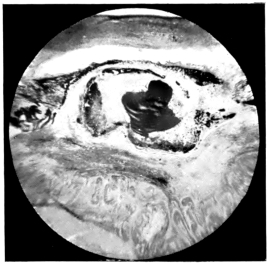

PLATE II.

FACING

PAGE

10.

LENS DISLOCATED BETWEEN CILIARY BODY AND SCLERA

curly bracket span

38

11.

NUCLEUS OF CATARACT FREELY MOVABLE BETWEEN THE AQUEOUS AND VITREOUS CHAMBERS

12.

LENS IMPACTED IN ANGLE OF ANTERIOR CHAMBER

13.

CAPSULE OF MORGAGNIAN CATARACT IMPACTED IN ANGLE OF ANTERIOR CHAMBER

14.

LENS FLOATING FREE IN VITREOUS CHAMBER

15.

LENS LIGHTLY IMPRISONED IN EXUDATE INTO VITREOUS CAVITY